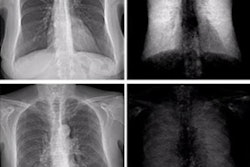

Image courtesy of Ran Zhang, PhD.During data acquisition, subjects are scanned in pulse mode (30 pulses per second) while the table moves along the superior-inferior (SI) direction. The detector readout is synchronized with the pulses. A slit-scan design allows scanning of the entire chest with a lateral coverage area of 32 centimeters along the SI direction with a scan speed of 7 cm per second, Zhang said.

Initial tests were performed using an anthropomorphic chest phantom. To simulate potential lung nodules, a container containing microbubble powder and calcium hydroxyapatite was attached to the chest phantom.

The estimated air kerma and effective dose were 53 uGy and 9.2 uSv, which is well below the effective dose for a typical chest x-ray (~20 uSv), Zhang said. The quality of the absorption contrast image matched that of conventional chest x-rays. In addition, the dark-field image revealed the microbubble and the calcium hydroxyapatite, which was invisible in the absorption image due to anatomical noise, Zhang said.

"Preliminary phantom and animal imaging results show promising image quality and contrast levels," he said.